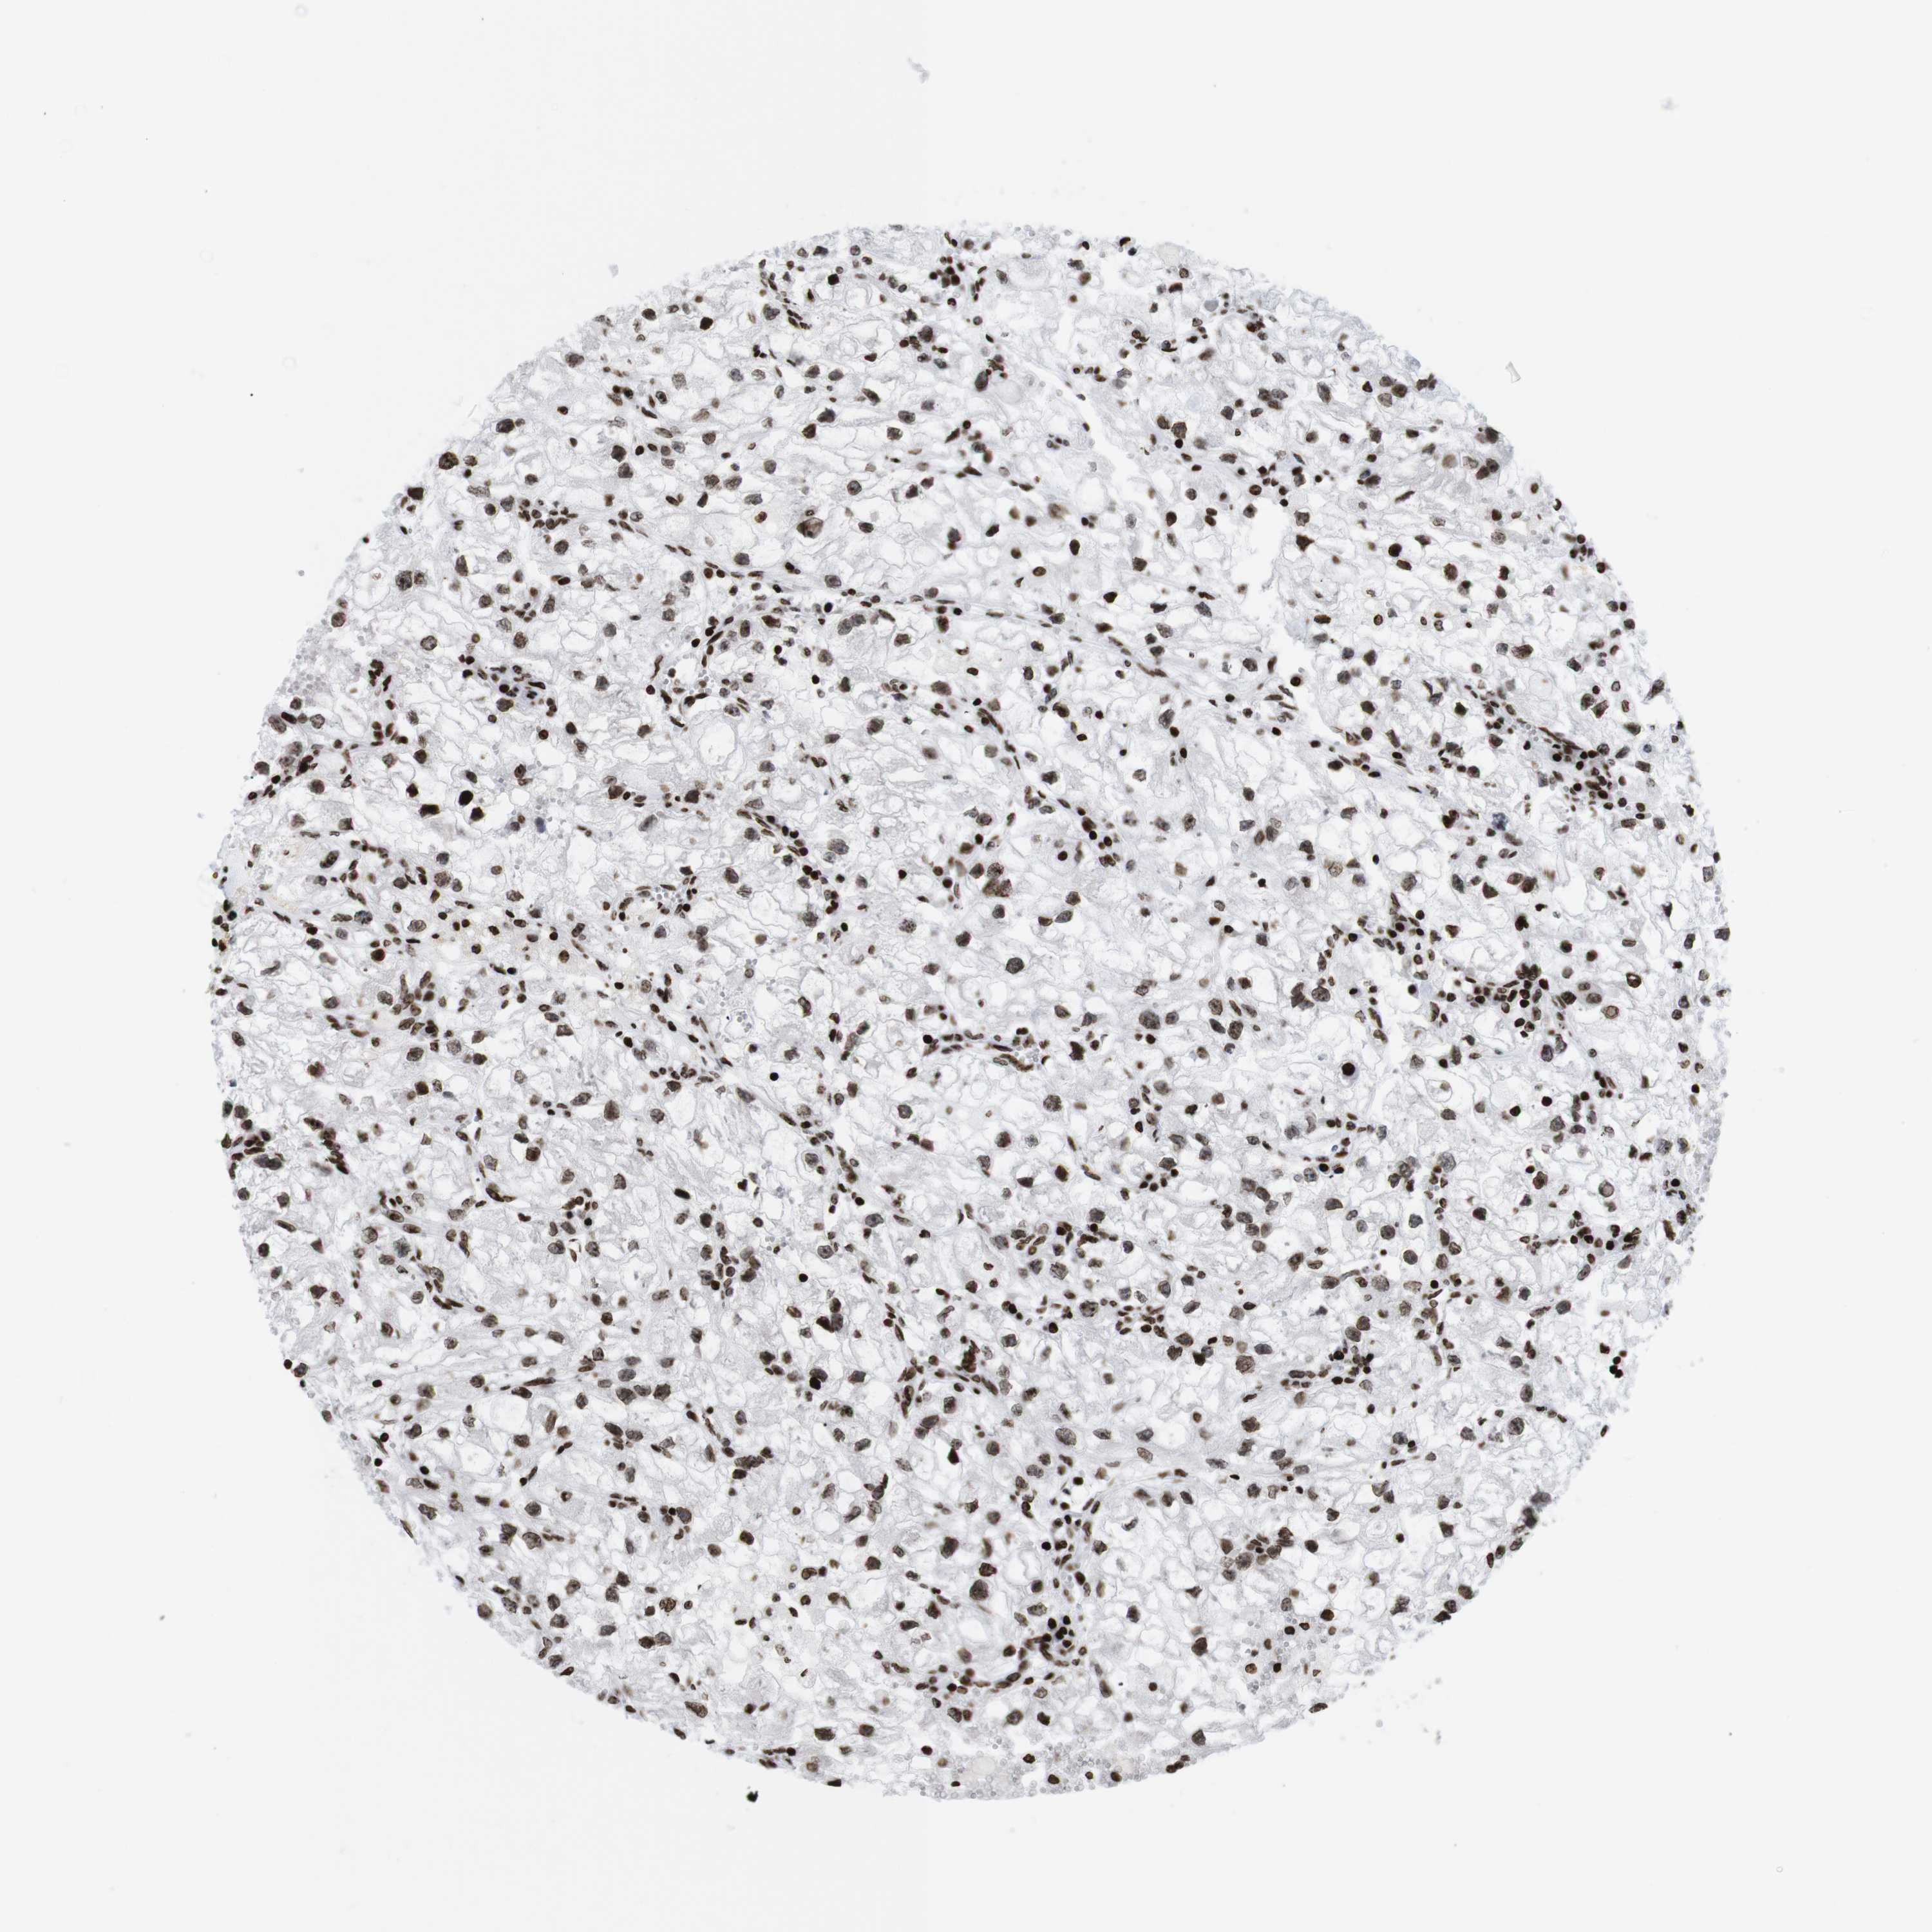

Average pTPM 2.2

Number of samples 521